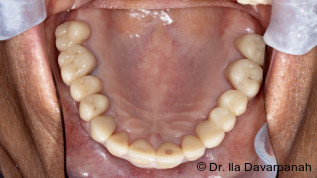

Eine kürzlich veröffentlichte Studie der Universität Göteborg bestätigt die Langlebigkeit von Zahnimplantaten. Dafür untersuchten die Forscher eine kleine Gruppe von Patienten, die zwischen 1982 und 1985 Einzelzahnimplantate erhalten hatten. Fast 40 Jahre später sind diese Implantate noch immer funktionstüchtig und stabil. Von den ursprünglich 16 Studienteilnehmern nahmen 13 an der Nachuntersuchung teil. Die Ergebnisse zeigen, dass alle 18 analysierten Implantate kaum Knochenverlust aufwiesen und fest im Kiefer verankert blieben.

Veröffentlicht wurde die Studie in der Fachzeitschrift "Clinical Implant Dentistry and Related Research" (doi:10.1111/cid.13443). Sie gilt als die weltweit längste Nachbeobachtungsstudie zu Einzelzahnimplantaten. Neben der mechanischen Stabilität der Implantate konnte auch eine gute biologische Integration festgestellt werden. Der geringe Knochenverlust, der über die Jahre dokumentiert wurde, bestätigt, dass die Osseointegration auch langfristig zuverlässig funktioniert. Das unterstreicht die Bedeutung einer sorgfältigen Planung und regelmäßigen Nachsorge für den langfristigen Erfolg von Implantaten.

Die Untersuchung zeigt zudem, dass die Implantate selbst zwar langlebig sind, die darauf befestigten Kronen jedoch eine kürzere Lebensdauer haben. Nach 40 Jahren waren nur noch etwa 60 % der ursprünglichen Kronen vorhanden, da viele im Laufe der Zeit aus ästhetischen Gründen ersetzt wurden. Jan Kowar, Prothetiker und Mitautor der Studie, sieht in der Weiterentwicklung neuer Kronenmaterialien eine Möglichkeit, Implantatbehandlungen zukünftig noch langlebiger zu machen.